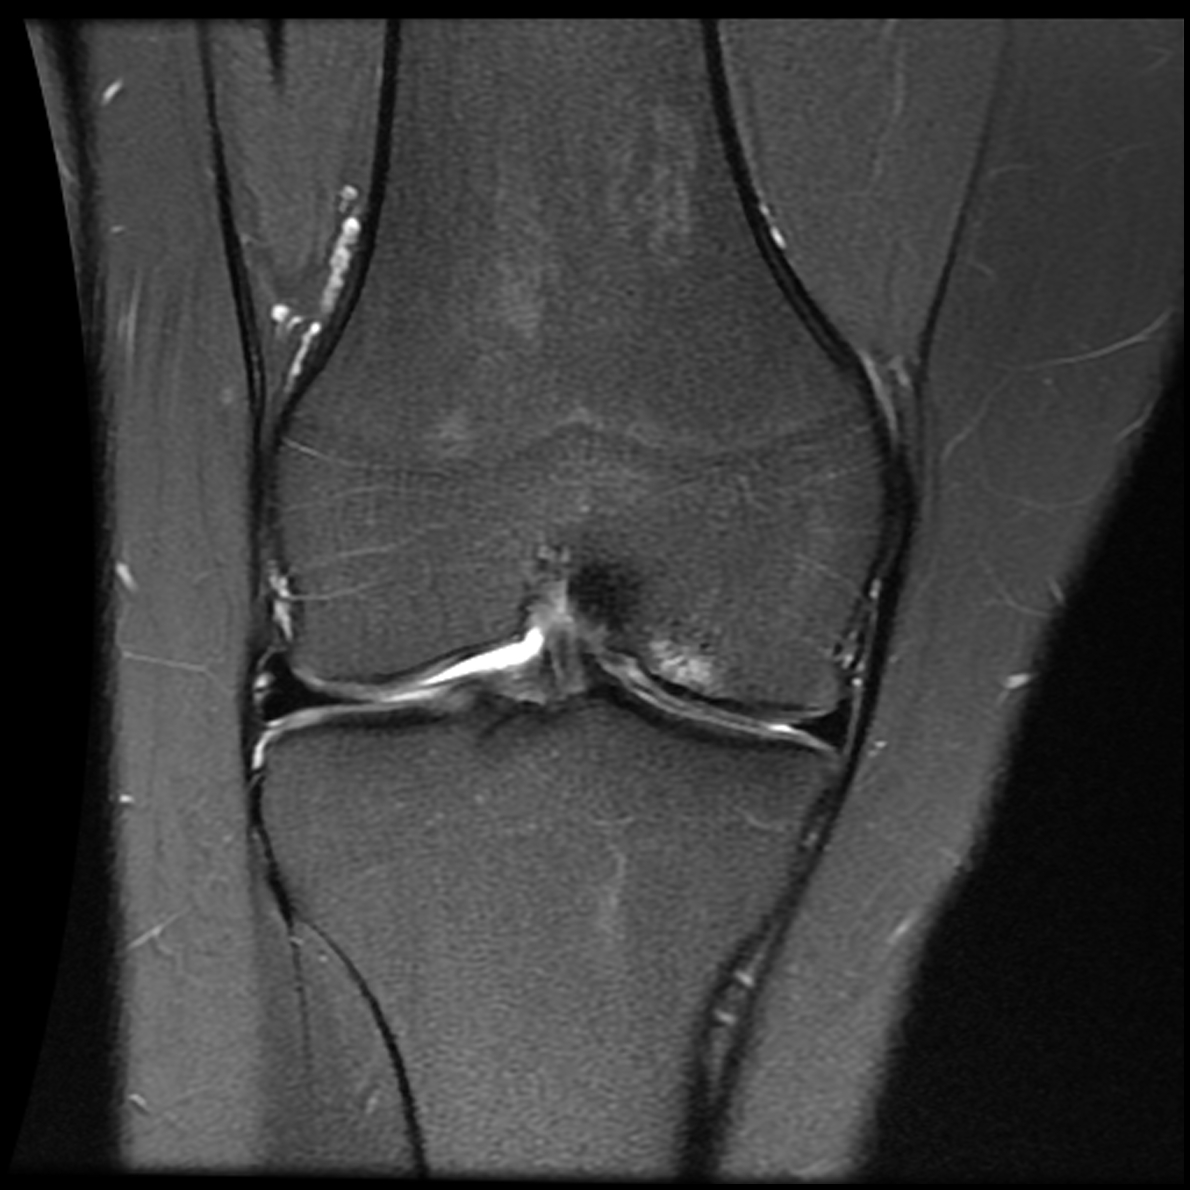

March 2019: Trampoline injury to right knee causing ACL tear, meniscus tear

March 2019: MRI 1

March 2019 MRI

IMPRESSION:

- Complete rupture proximal third anterior cruciate ligament with pivot shift

pattern of bone injuries lateral compartment and contrecoup bone contusion

medial tibial plateau. Joint hemarthrosis. - Complex tear lateral meniscus with inferiorly flipped flap tear extending

into the popliteal hiatus. - Complex tear medial meniscus with outwardly extruded tears of the posterior

horn and body. - Low-grade sprains medial collateral ligament and medial posterior oblique

ligament. - Low-grade sprains fibular collateral ligament and anterolateral ligament.

Intermediate to high-grade sprain popliteofibular ligament and arcuate ligament. - Grade 1 strains vastus lateralis, short head biceps, sartorius, soleus,

popliteus and anterior compartment muscles.